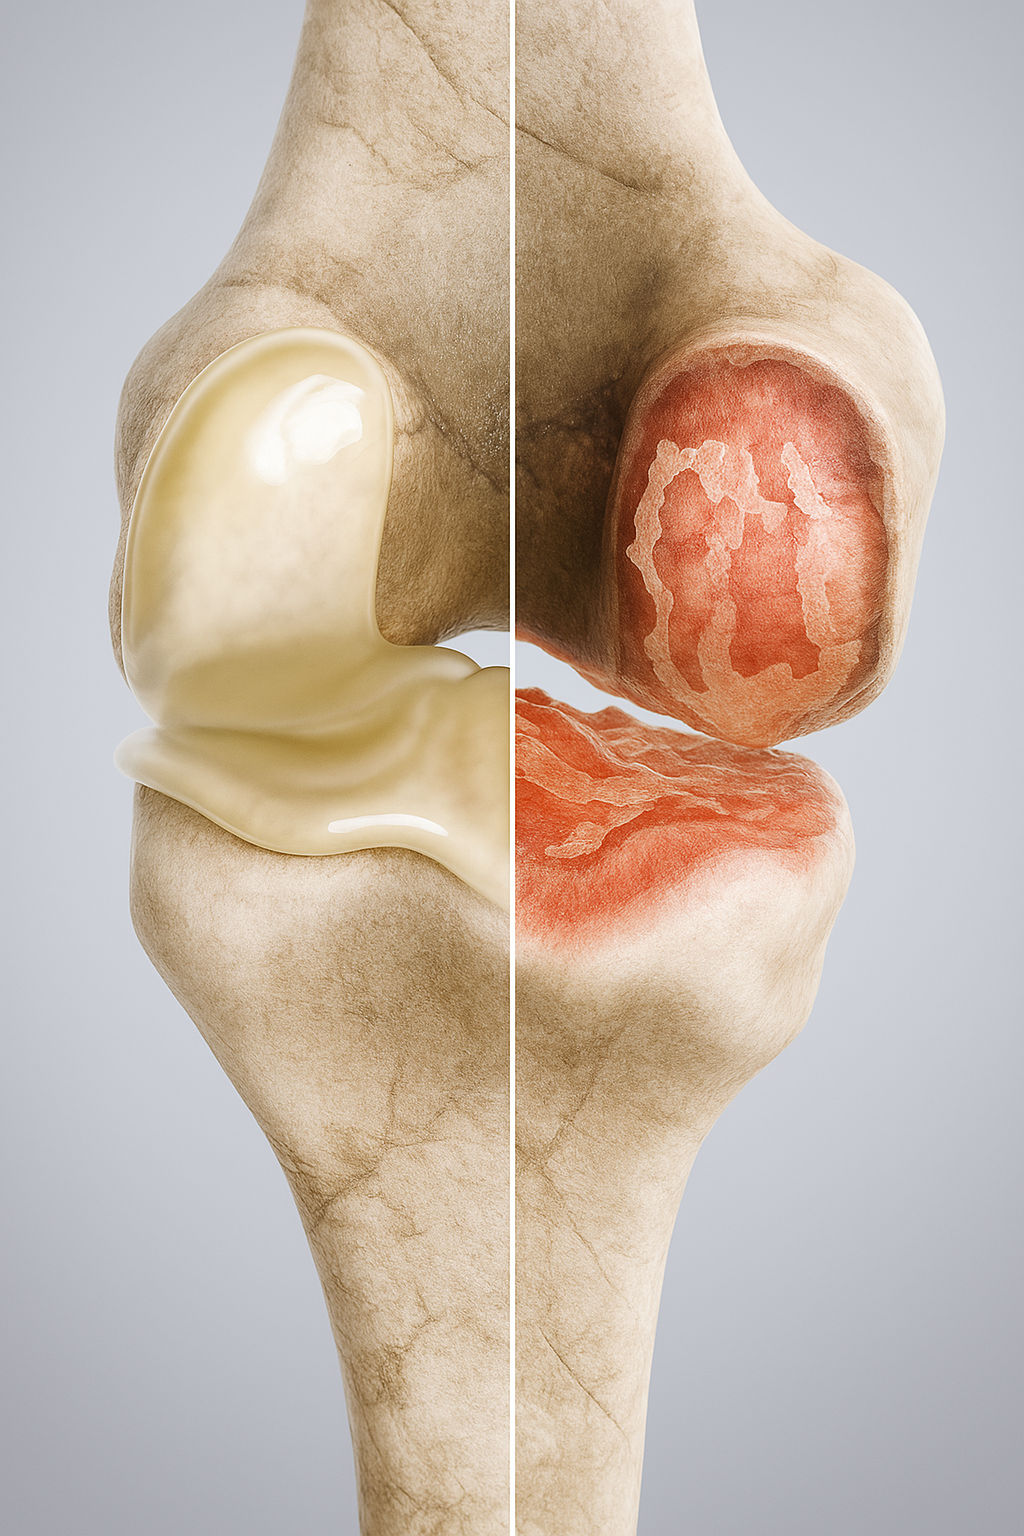

Как возникает остеоартроз

Сложный процесс формирования остеоартроза еще не выяснен.

Ортопеды и хирурги могут лечить симптомы, но этиологическое излечение пока невозможно.

Известно, что такие факторы, как перегрузка или неадекватное напряжение сустава, а также травмы костей, хрящей или связок благоприятствуют формирование остеоартроза коленного сустава.

Боль — основной симптом и одно из первых проявлений остеоартроза коленного сустава.

При поражении внутреннего (медиального) мыщелка боль обычно локализуется по внутренней поверхности колена и усиливается при ходьбе, спуске или подъёме по лестнице. Со временем она может появляться даже в покое.

Чтобы уменьшить дискомфорт, человек инстинктивно снижает нагрузку на больную ногу и ограничивает движения. Однако неподвижность приводит к ухудшению состояния хряща, так как для его питания необходимо постоянное движение суставных поверхностей. В результате развивается тугоподвижность, ослабление мышц бедра и голени, а также изменение оси конечности.

Наиболее распространённой формой заболевания является первичный остеоартроз, возникающий без очевидной причины — чаще у людей старшего возраста из-за естественного износа суставных структур.

Иногда артроз внутреннего мыщелка развивается вторично — после травм, нестабильности колена или воспалительных заболеваний.

При хронических воспалительных процессах например, при ревматоидном артрите, организм вырабатывает вещества, вызывающие отёк и утолщение синовиальной оболочки. Это приводит к постоянному воспалению и постепенному разрушению хряща и костной ткани.